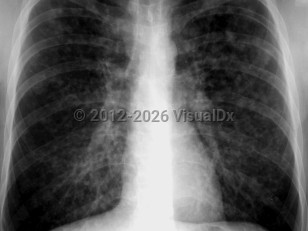

Acute respiratory distress syndromeAcute respiratory distress syndrome